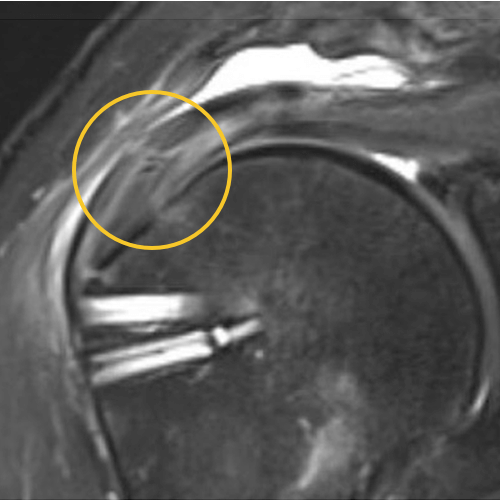

We published this case study in the JOEI (Journal of Orthopedic Experience and Innovation) Journal. We did a revision of the large type-II repair and augmented it with BioBrace®. You can see the pre-op and three-month MRI below. Still fluid in the subacromial space but that tendon is clearly coming across into the footprint. Then, an eight-month MRI shows there's no further fluid in the subacromial space and maturation of that repair across the footprint.

Pre-OP

3 Months

8 Months

This is a patient that’s been in pain for quite some time and was clinically improving. You can see the outcome scores show dramatic improvement.